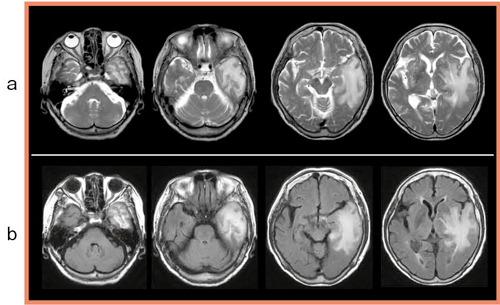

MRIのT2強調画像では,左側頭葉に広範なT2延長域があり,脳ヘルニアを起こしている状態であった(図3a)。FLAIRの画像でも,腫脹を伴う広範な左側頭葉の病変が認められる(図3b)。

T1強調画像と造影後の画像では,病変はT1延長を呈するところが主体となっているが,一部出血を思わせる高信号域が認められた。造影後のT1強調画像では,側頭葉の底部が主に増強されていた。

拡散強調画像(DWI)およびADC mapでは拡散制限は強くなく,脳外科医は神経膠腫と判断していた。

T2*強調画像では,微小な出血が確認された。術前のルーチンで造影後MRAを撮像したが,圧排はあるものの,主幹動脈などに特に問題は認められなかった。

図3 症例の頭部MRI画像

a:T2強調画像

b:FLAIR

脳外科では脳腫瘍疑いで,急速に進行していることからすぐにも手術を行うとの見解であったが,疑問の残る点もあった。図4aをよく見ると,左の横静脈洞からS状静脈洞にかけ,flow voidが消失している(←)。しかし,左S状静脈洞には,増強欠損域はなかった(図4b←)。

図4 症例の頭部MRI画像

a:左の横静脈洞からS状静脈洞にかけ,flow voidが消失している(←)。

b:造影後T1強調画像では,S状静脈洞に増強欠損域は認められない(←)。

これらのMRIの所見からは,静脈洞血栓症と診断するには説得力が不足しているため,Aquilion ONEによるCT撮影を行うこととした。